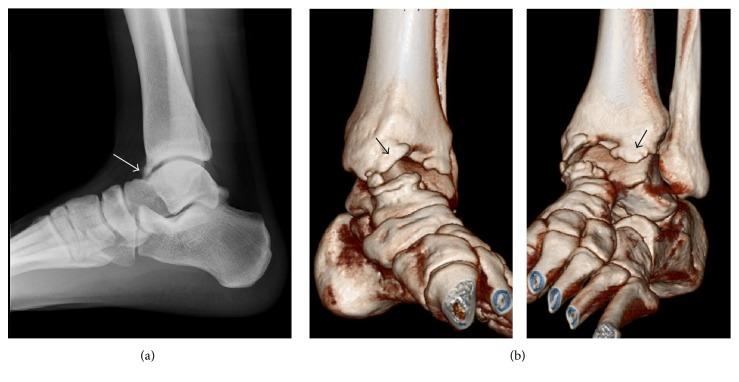

一名足球运动员踝关节镜检查后胫前动脉假性动脉瘤

当使用标准的前外侧和前内侧入路时,踝关节镜检查出现血管并发症的风险较低。然而,踝关节前方脂肪垫的厚度对薄壁的胫前动脉几乎没有保护作用,这使得它在踝关节前方关节手术过程中容易受到间接损伤。据我们所知,文献中仅描述了11例踝关节镜检查后累及胫前动脉的假性动脉瘤病例。在此,我们报告了一例罕见病例,一名19岁的足球运动员在使用踝关节撑开方法进行踝关节镜检查后出现胫前动脉假性动脉瘤,并接受了胫前动脉损伤吻合术。踝关节过度撑开使神经血管结构在踝关节镜检查期间发生胫前动脉医源性损伤的风险更高。外科医生在踝关节镜检查后应仔细观察踝关节术后肿胀和疼痛情况。